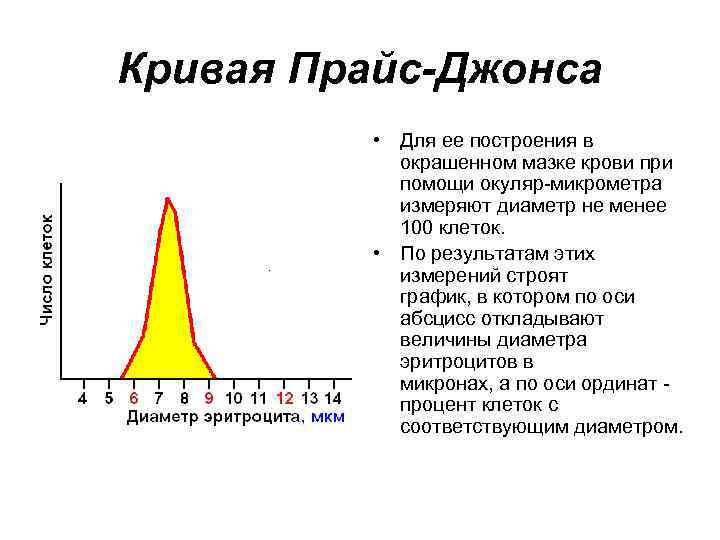

Кривая Прайс-Джонса • Для ее построения в окрашенном мазке крови при помощи окуляр-микрометра измеряют диаметр не менее 100 клеток. • По результатам этих измерений строят график, в котором по оси абсцисс откладывают величины диаметра эритроцитов в микронах, а по оси ординат - процент клеток с соответствующим диаметром.

Кривая Прайс-Джонса • Для ее построения в окрашенном мазке крови при помощи окуляр-микрометра измеряют диаметр не менее 100 клеток. • По результатам этих измерений строят график, в котором по оси абсцисс откладывают величины диаметра эритроцитов в микронах, а по оси ординат - процент клеток с соответствующим диаметром.

• Эритроцитометрическая кривая у здоровых людей имеет правильную треугольную форму с высокой вершиной и узким основанием. • Преобладают эритроциты с диаметром 6 -8 мкм, которые составляют 70 -75% всех эритроцитов. • На долю микроцитов (клетки диаметром меньше 6 мкм) и макроцитов (диаметр более 8 мкм) приходится приблизительно одинаковое количество (12 -15%), ширина кривой отражает степень анизоцитоза, а положение максимума - средний диаметр эритроцита.

• Эритроцитометрическая кривая у здоровых людей имеет правильную треугольную форму с высокой вершиной и узким основанием. • Преобладают эритроциты с диаметром 6 -8 мкм, которые составляют 70 -75% всех эритроцитов. • На долю микроцитов (клетки диаметром меньше 6 мкм) и макроцитов (диаметр более 8 мкм) приходится приблизительно одинаковое количество (12 -15%), ширина кривой отражает степень анизоцитоза, а положение максимума - средний диаметр эритроцита.